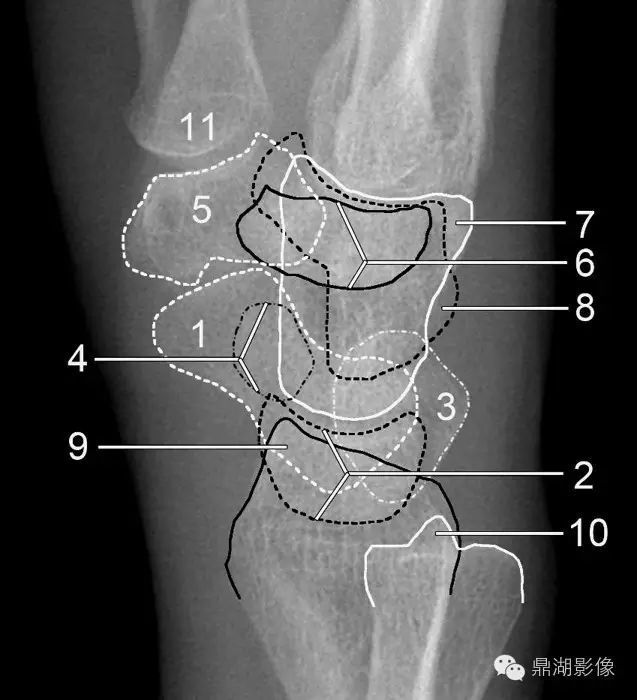

腕关节骨骼解剖图

腕关节骨骼解剖图,

又称桡腕关节,由桡骨下端的关节面和尺骨头下方的关节盘作为关节窝

必点收藏腕关节详细解剖及影像对照

腕关节大全解剖骨折脱位值得收藏

x线高清图谱精致腕关节解剖